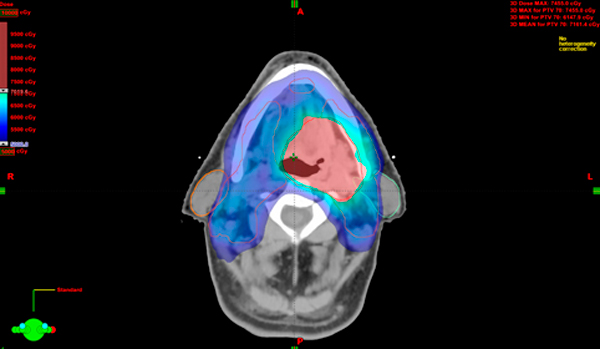

Plan de tratamiento que muestra un zona (rosada) de alta dosis a nivel del tumor. Una zona (azul) de dosis intermedia que trata áreas ganglionares y zonas de bajo riesgo. Se puede observar, que la irradiación es mínima en estructuras sensibles como la medula espinal y las glándulas parótidas.

El sistema de planificación brinda imágenes que muestran cómo se distribuye la radiación.